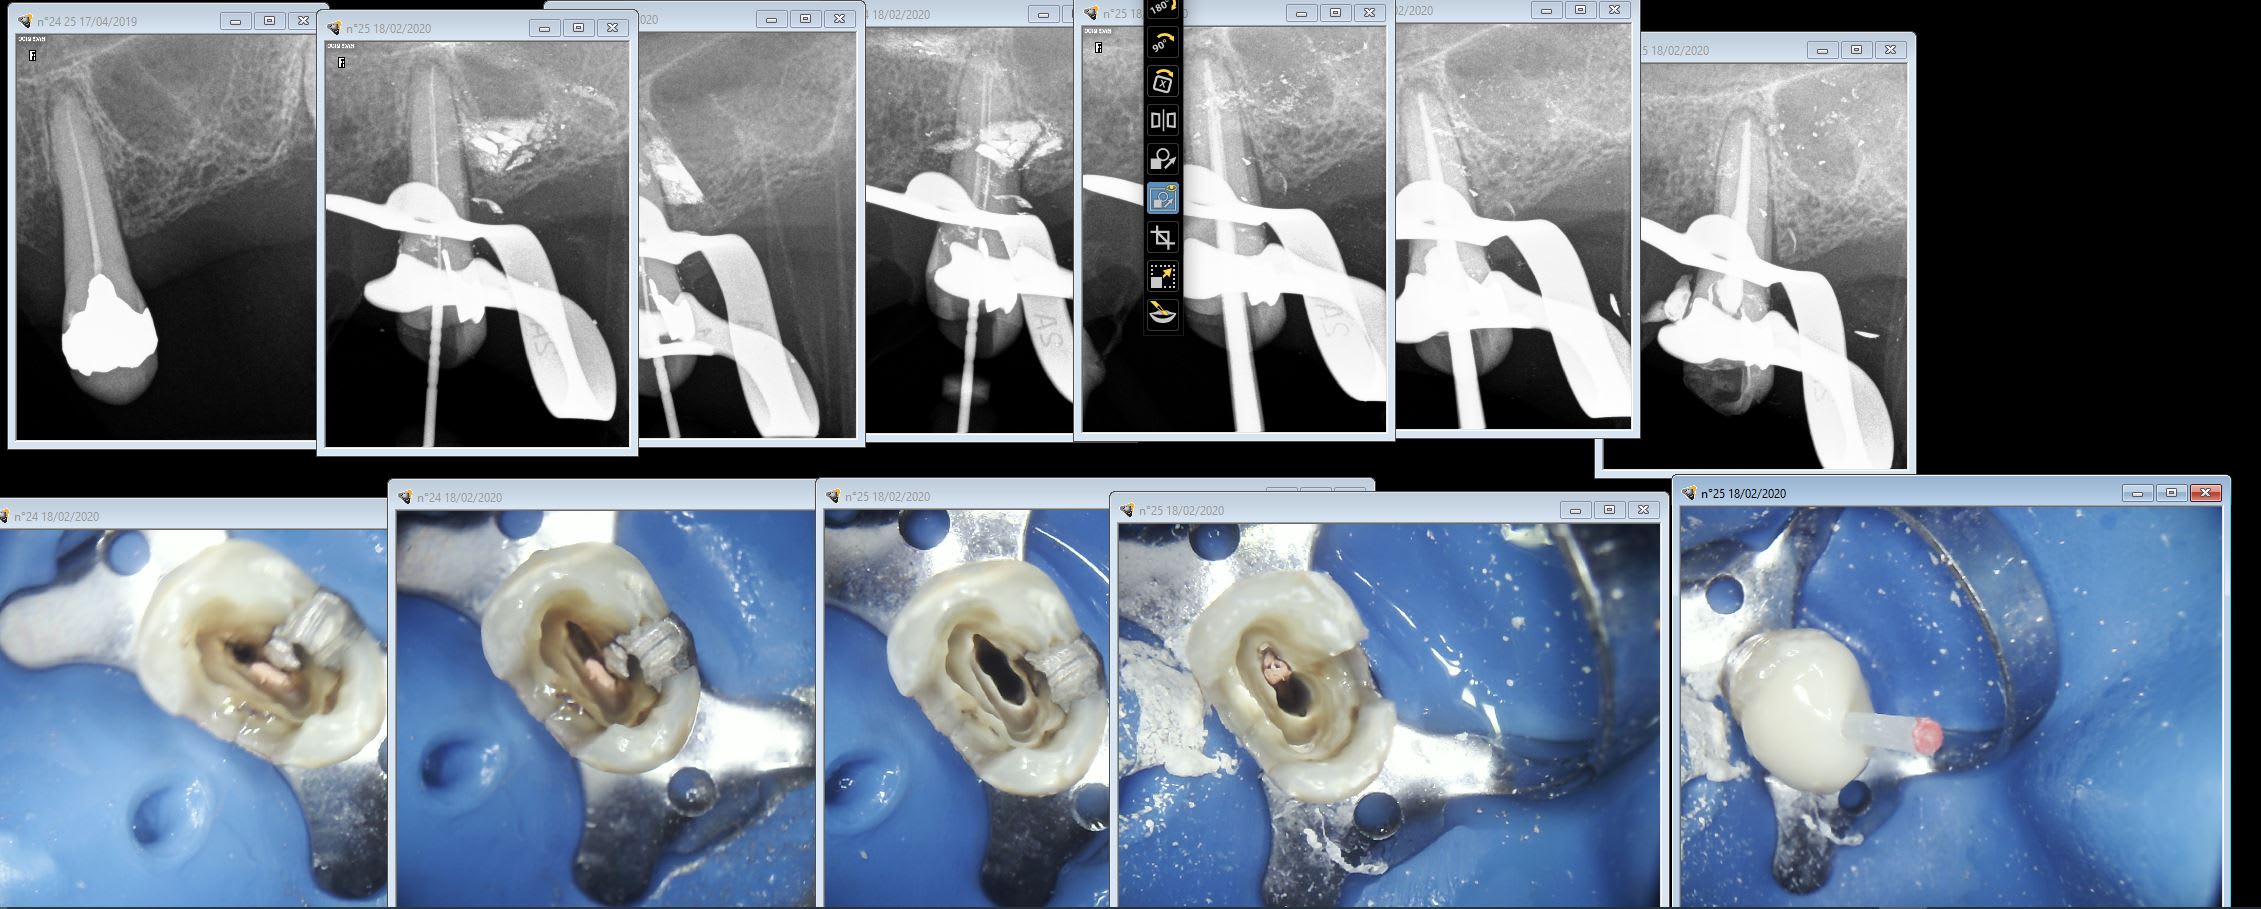

Rte 25 rio1at - Eugenol

Capture d écran 2018 05 16 à 21.30 - Eugenol

Daryl

19/02/2020 à 09h36

ça s'achète où ces limes d'iirigation Eddy ?? Directement chez Dentsply ?? Merci ;-)

Utilisateur banni

19/02/2020 à 12h06

Il est toujours là gai-luron ? Voici la junior technique dont on avait parlé , c’est à dire la wash technique sans avoir besoin d’évider ton empreinte ou de mettre un film plastique ou autre .

1) du lourd. J’enlève mon PE, je remets mon PE en bouche, j’enlève je remets etc etc => les zones de manque correspondent au zones qui vont permettre de remettre le PE sans évider

2) du light

--

La forme de ma coupe de cheveux futuriste me permet une meilleure pénétration dans l'air et d' avoir moins de résistance face au vent lorsque je me déplace.

6f9c9f24 a8cd 43ff ae86 a410ca8b6a72 bqu5tx - Eugenol

Fac52c24 d661 40d6 8d84 e679f903cefd gi50bi - Eugenol